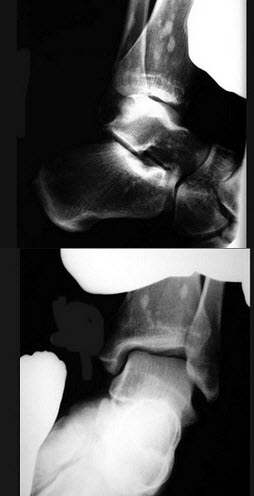

男,56岁,踝关节肿胀,有糖尿病史,结合图像,最可能的诊断是()

A.创伤性关节炎

B.退行性关节病

C.痛风

D.类风湿关节炎

E.神经性关节病